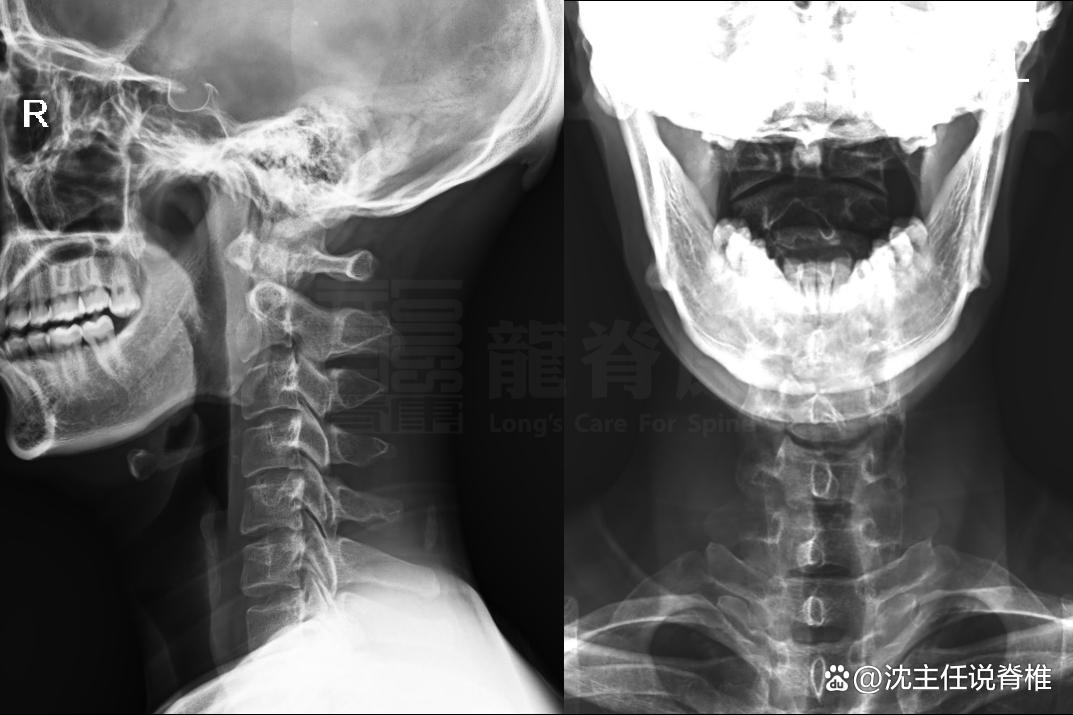

交感神经型颈椎病症状

1、头痛多为单侧头部疼痛,性质可为胀痛刺痛,部位集中在枕部或顶部,与颈椎病变节段相关颈部活动可能诱发或加重头痛,机制与颈椎病变刺激交感神经导致头部血管舒缩功能紊乱有关长期伏案工作或颈部姿势不良者更易出现眼部症状包括眼...